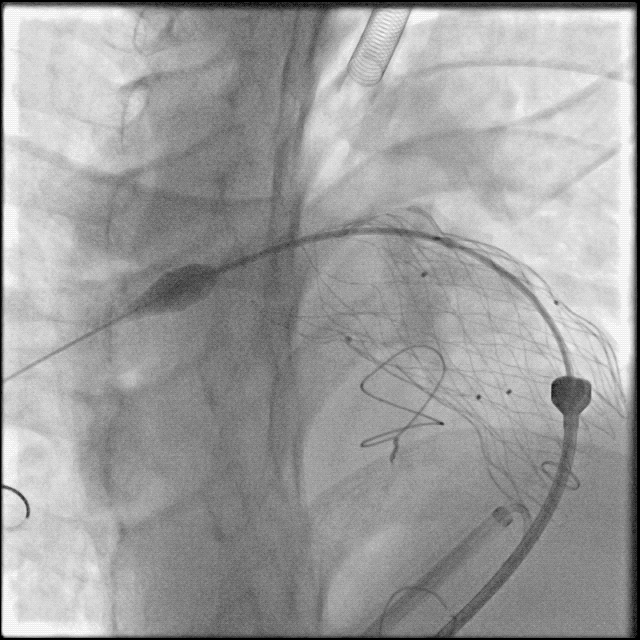

术中肺动脉造影:

重度肺动脉瓣关闭不全,大量返流。

肺动脉造影测量肺动脉内径等参数:

送入输送系统:

根据术前CT、术中造影及球囊测量结果,选择P34-25型号的VenusP-Valve瓣膜,使用圈套器辅助,沿超硬导丝送输送器至肺动脉分叉处。

缓慢释放瓣膜,造影确认人工瓣膜起始位置准确:

继续释放瓣膜,反复造影确认人工瓣膜位置准确:

人工瓣膜释放完成,缓慢退出输送器:

造影确认无明显瓣周漏: